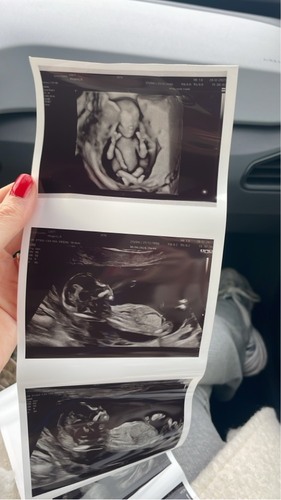

Je kan er denk ik bijna niet om heen😂, maar wat denken jullie?

Nee haha hier kun je niet bepaald omheen 😂😂😂 ik zie geen Hamburger 🍔 maar echt een banaan met kiwi 😂😂😂